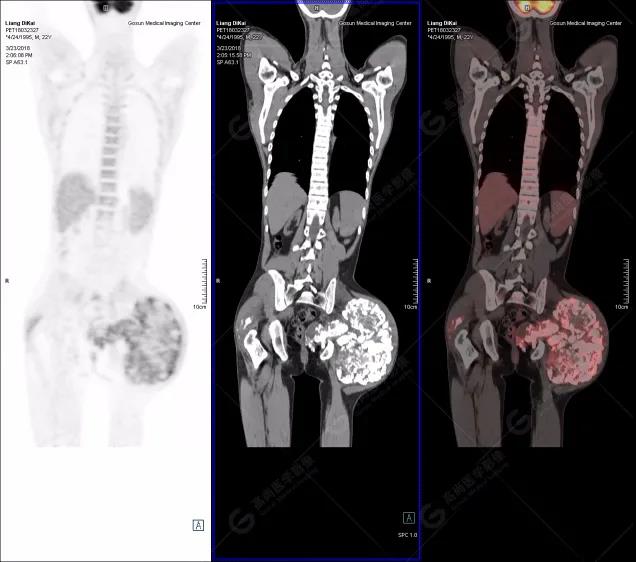

本中心PET/CT提示

1.右肘關(guān)節(jié)周圍、骶尾部皮下、雙側(cè)臀部、盆腔左側(cè)壁及左側(cè)大腿根部肌肉、肌間隙多發(fā)結(jié)節(jié)狀、片塊狀及不規(guī)則巨塊狀高密度鈣化灶,伴代謝不均勻輕度增高,考慮為鈣質(zhì)沉著癥;

2.甲狀腺雙葉后方多發(fā)(右2個,左1個)小結(jié)節(jié)狀軟組織影,部分代謝輕度增高,多考慮為甲狀旁腺腺瘤。